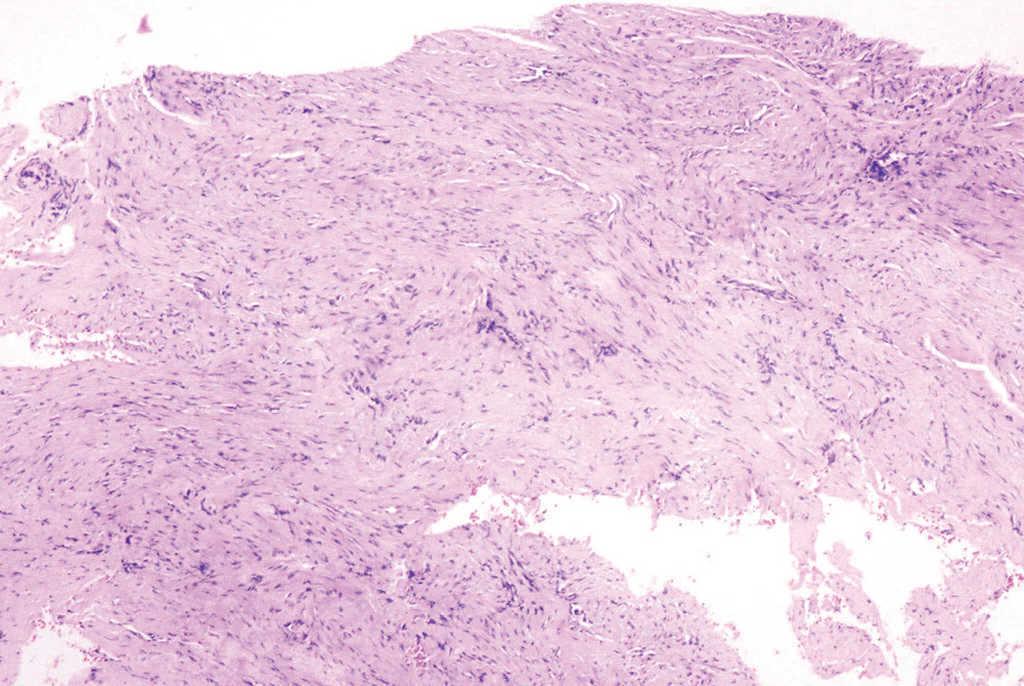

En la primera visita se realizó una analítica general, que no mostró hallazgos patológicos, y una serología viral, incluyendo virus exantemáticos, que resultó negativa. La radiografía de la mano sólo mostraba un engrosamiento focal de partes blandas, sin afectación ósea subyacente. Se revisaron las biopsias correspondientes a la lesiones extirpadas inicialmente (figs. 3-5).

Fig. 3.--La biopsia mostraba una tumoración mal delimitada situada en dermis y tejido celular subcutáneo. (Hematoxilina-eosina, x40.)

El examen histopatológico correspondiente a la extirpación previamente realizada mostraba una proliferación mal delimitada localizada en la dermis y el tejido celular subcutáneo, que se extendía hasta la unión dermoepidérmica, compuesta por fascículos entrelazados de células fusiformes (figs. 3 y 4). No se observaban células ni mitosis atípicas. A mayor aumento, en el citoplasma de algunas de estas células se apreciaba la presencia de inclusiones intracitoplasmáticas eosinofílicas, algunas de localización perinuclear (fig. 5). No se realizó estudio inmunohistoquímico.